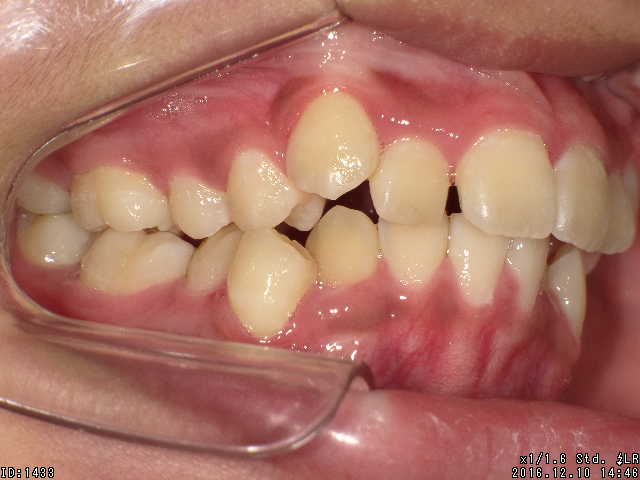

矯正前